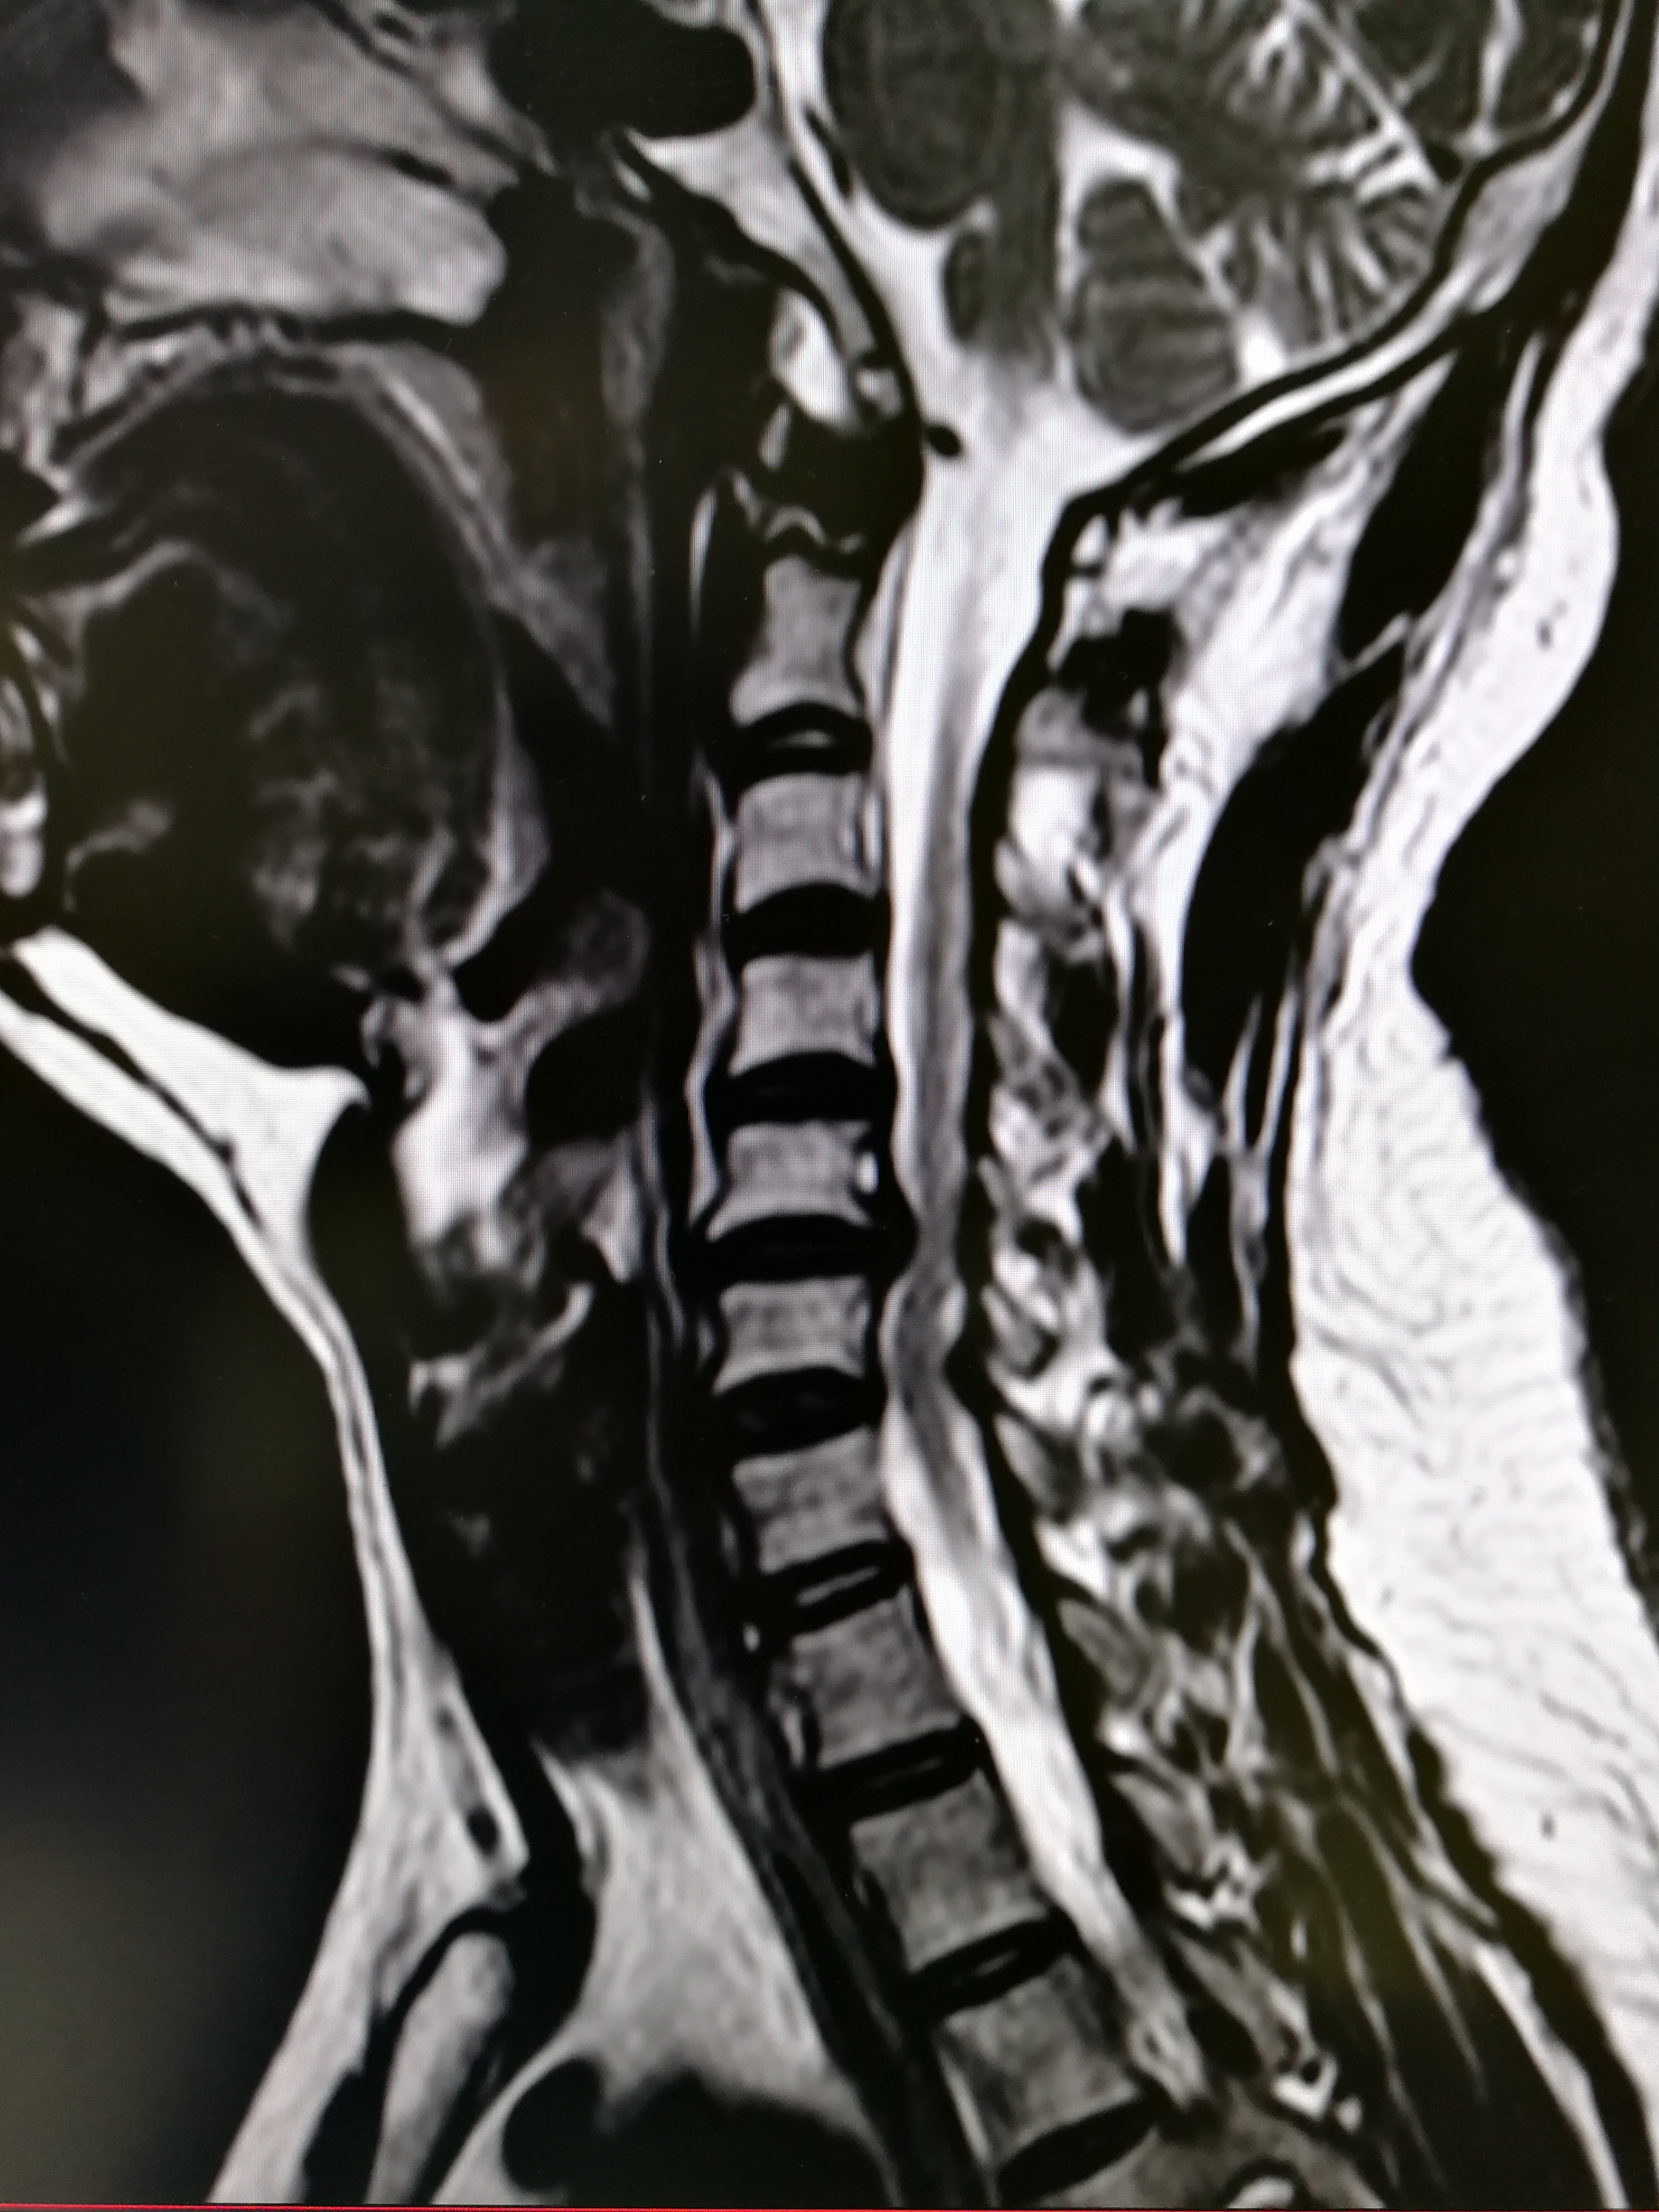

脊椎退行性变

2976x3968 - 1475KB - JPEG